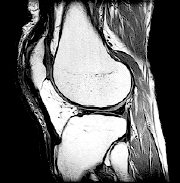

MRI. This detailed imaging test can show bone, cartilage, ligament, or muscle problems, without using X-rays.

| Imaging tests such as an MRI scan may help your healthcare provider find the cause of your knee problem. |